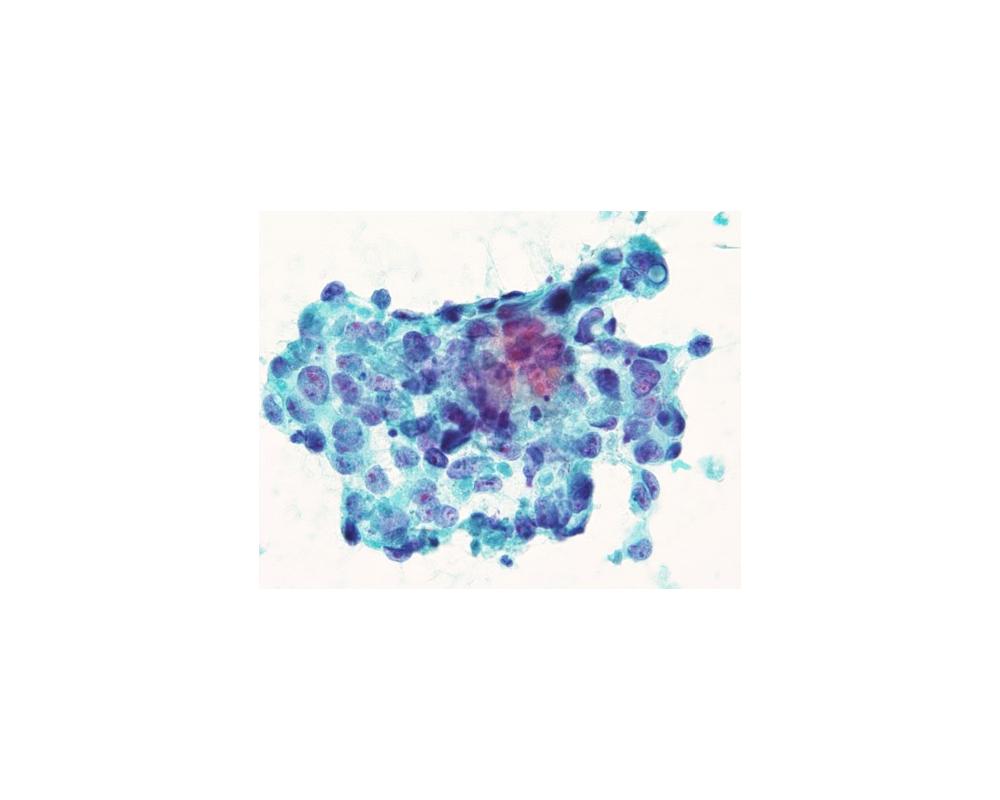

第40回日本臨床細胞学会九州連合会学会(大分)スライドカンファレンス症例2

種別:呼吸器

出題:今村 彰吾 独立行政法人国立病院機構九州がんセンター

| 年齢 | 50歳代 | 性別 | 女性 |

| 採取部位 | 気管支 | 採取方法 | 気管支鏡下生検捺印 |

既往歴 右頬粘膜癌(7年前)および肺転移(8年前)、歯肉癌(2か月前)

現病歴 右頬粘膜癌に対してニボルマブ投与中、PET-CTにて左気管支内に異常集積を指摘され、精査目的で当科紹介受診となった。

| 正解 | 5.間葉系腫瘍 |

▼選択肢及び投票結果

| 1.扁平上皮化生細胞 | 4件 | (3.8%) | |

| 2.扁平上皮癌 | 6件 | (5.7%) | |

| 3.腺癌 | 0件 | (0.0%) | |

| 4.非小細胞癌(肉腫様癌) | 35件 | (33.3%) | |

| 5.間葉系腫瘍 | 60件 | (57.1%) | |

| 投票総数 | 105件 | (100%) |